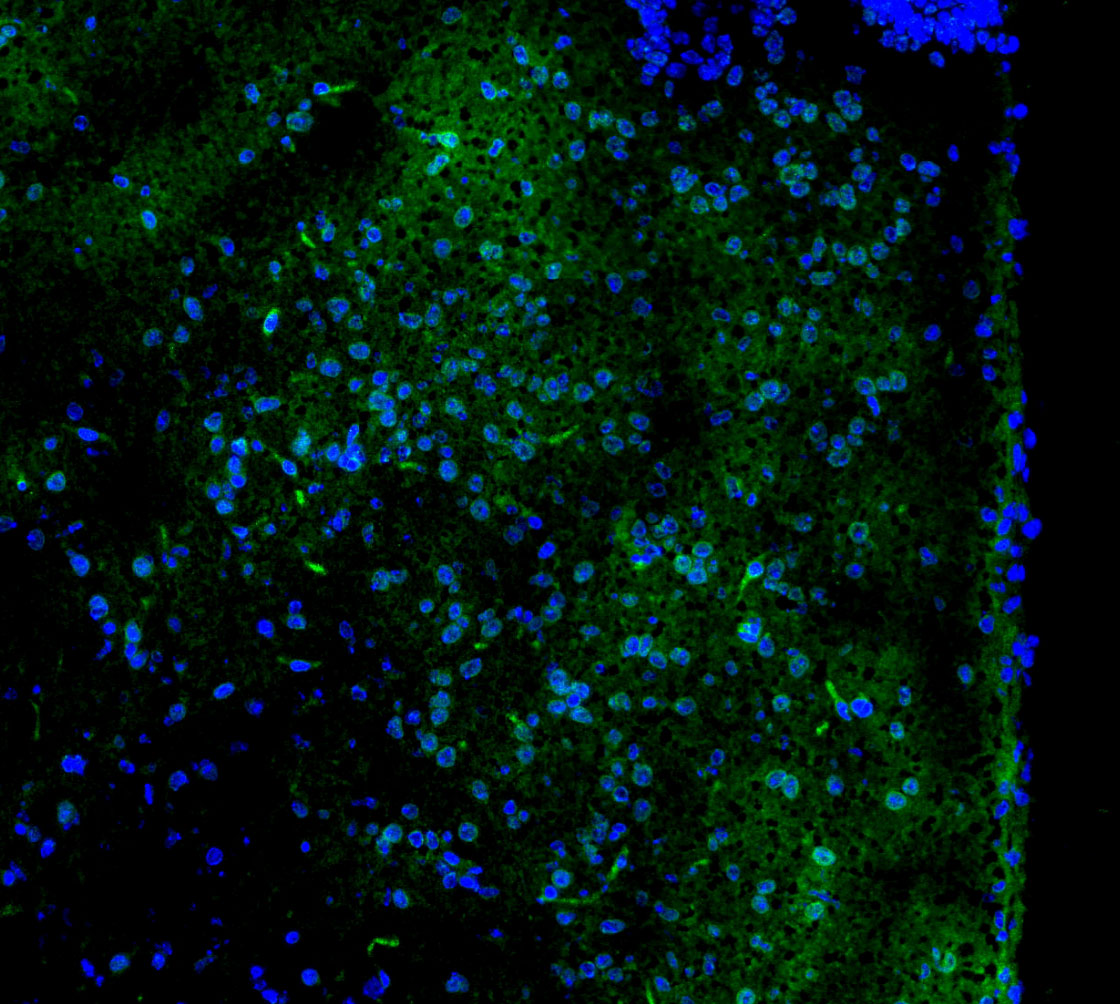

• Immunofluorescent analysis of mouse brain tissue using F0780 (green, 1:50) and Hoechst (blue).